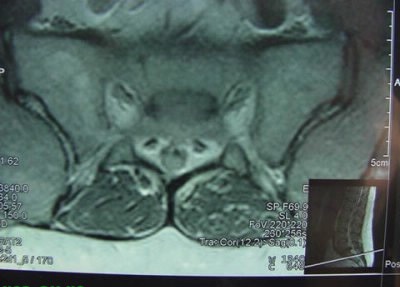

Phim chụp X-quang không bình thường

Một người tên Mark đã nhìn thấy những điều kỳ lạ như thế trong những tấm phim X-quang chụp xương sống của mình. Anh bị chứng đau lưng kinh niên vì bị thoái vị các đốt xương và trong lần khám định kỳ bác sĩ đã rất ngạc nhiên sau khi xem phim chụp. Ngạc nhiên ở chỗ tại nơi thoái vị tất cả đều đúng trật tự. Mark thậm chí còn nói đùa với kết luận này: “Trong lưng của tôi giống con chuột đang bay và… Có khả năng tôi cần làm lễ với thầy phù thuỷ hơn là phẫu thuật xương sống…”